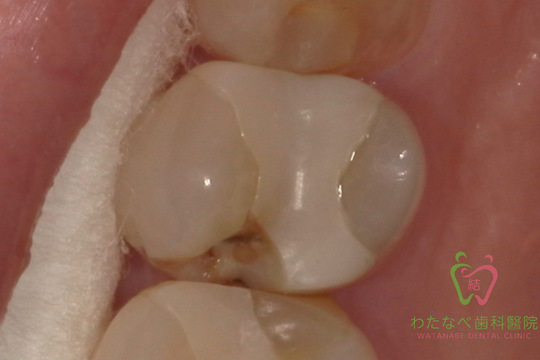

小さな奥歯の症例写真

前の歯医者でいれた詰め物が割れた

Before

40代・女性

オールセラミック

割れてしまった詰め物を除去。

下地の薬を入れ、形を整え、型取り。

本接着をし、終了。

2回

強い衝撃を与えると割れることがあります。

\55,000-(税込)